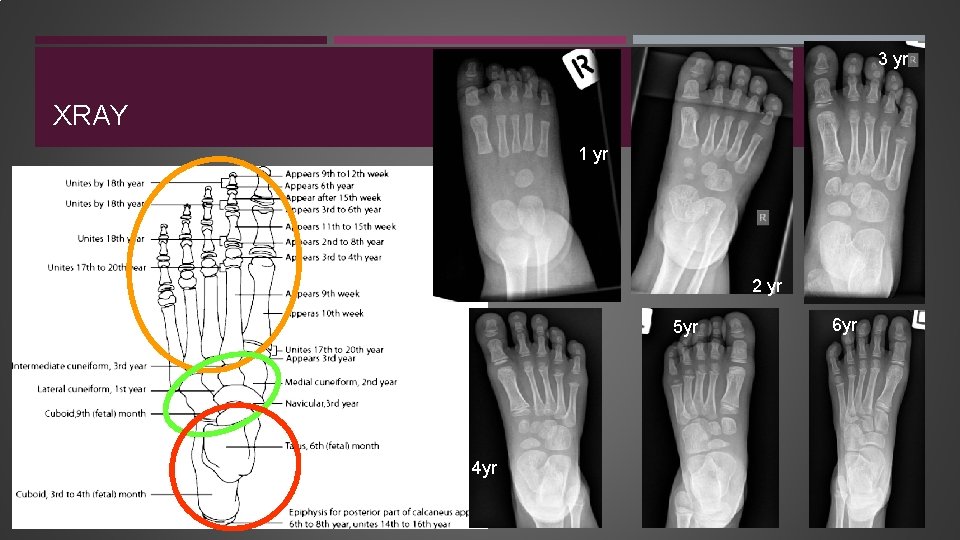

3 yr XRAY 1 yr 2 yr 5 yr 4 yr 6 yr